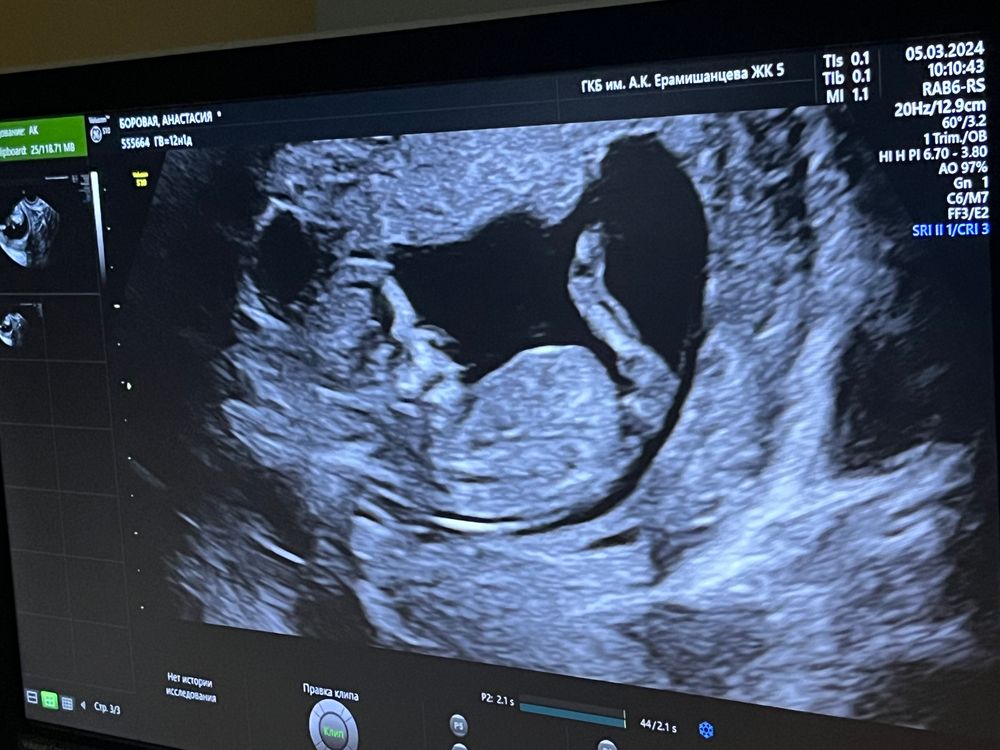

Ася в Зачатие 2 года Есть намеки на пол? Понимаю что рано , но вдруг 😅 Фолликулометрия Посмотрите еще 20 записей на эту тему Лучший ответ Алёна Хаустова Бугорка не видно 09.03.2024 Ответить Отменить Ответить Lolova Не видно и рано 09.03.2024 Ответить Свет У вас дама))) мое 13 недель + нипт, что мальчик 09.03.2024 Ответить Ксения Девочка 09.03.2024 Ответить Мария //рожу дочку в 2021// Не видно 09.03.2024 Ответить Помогите разобраться с УЗИ. Узи, видимо рано) Чаты Беременных Выберите чат: Январята-2026 Февралята-2026 Мартята-2026 Апрелята-2026 Майчата-2026 Июнята-2026 Июлята-2026 Августята-2026